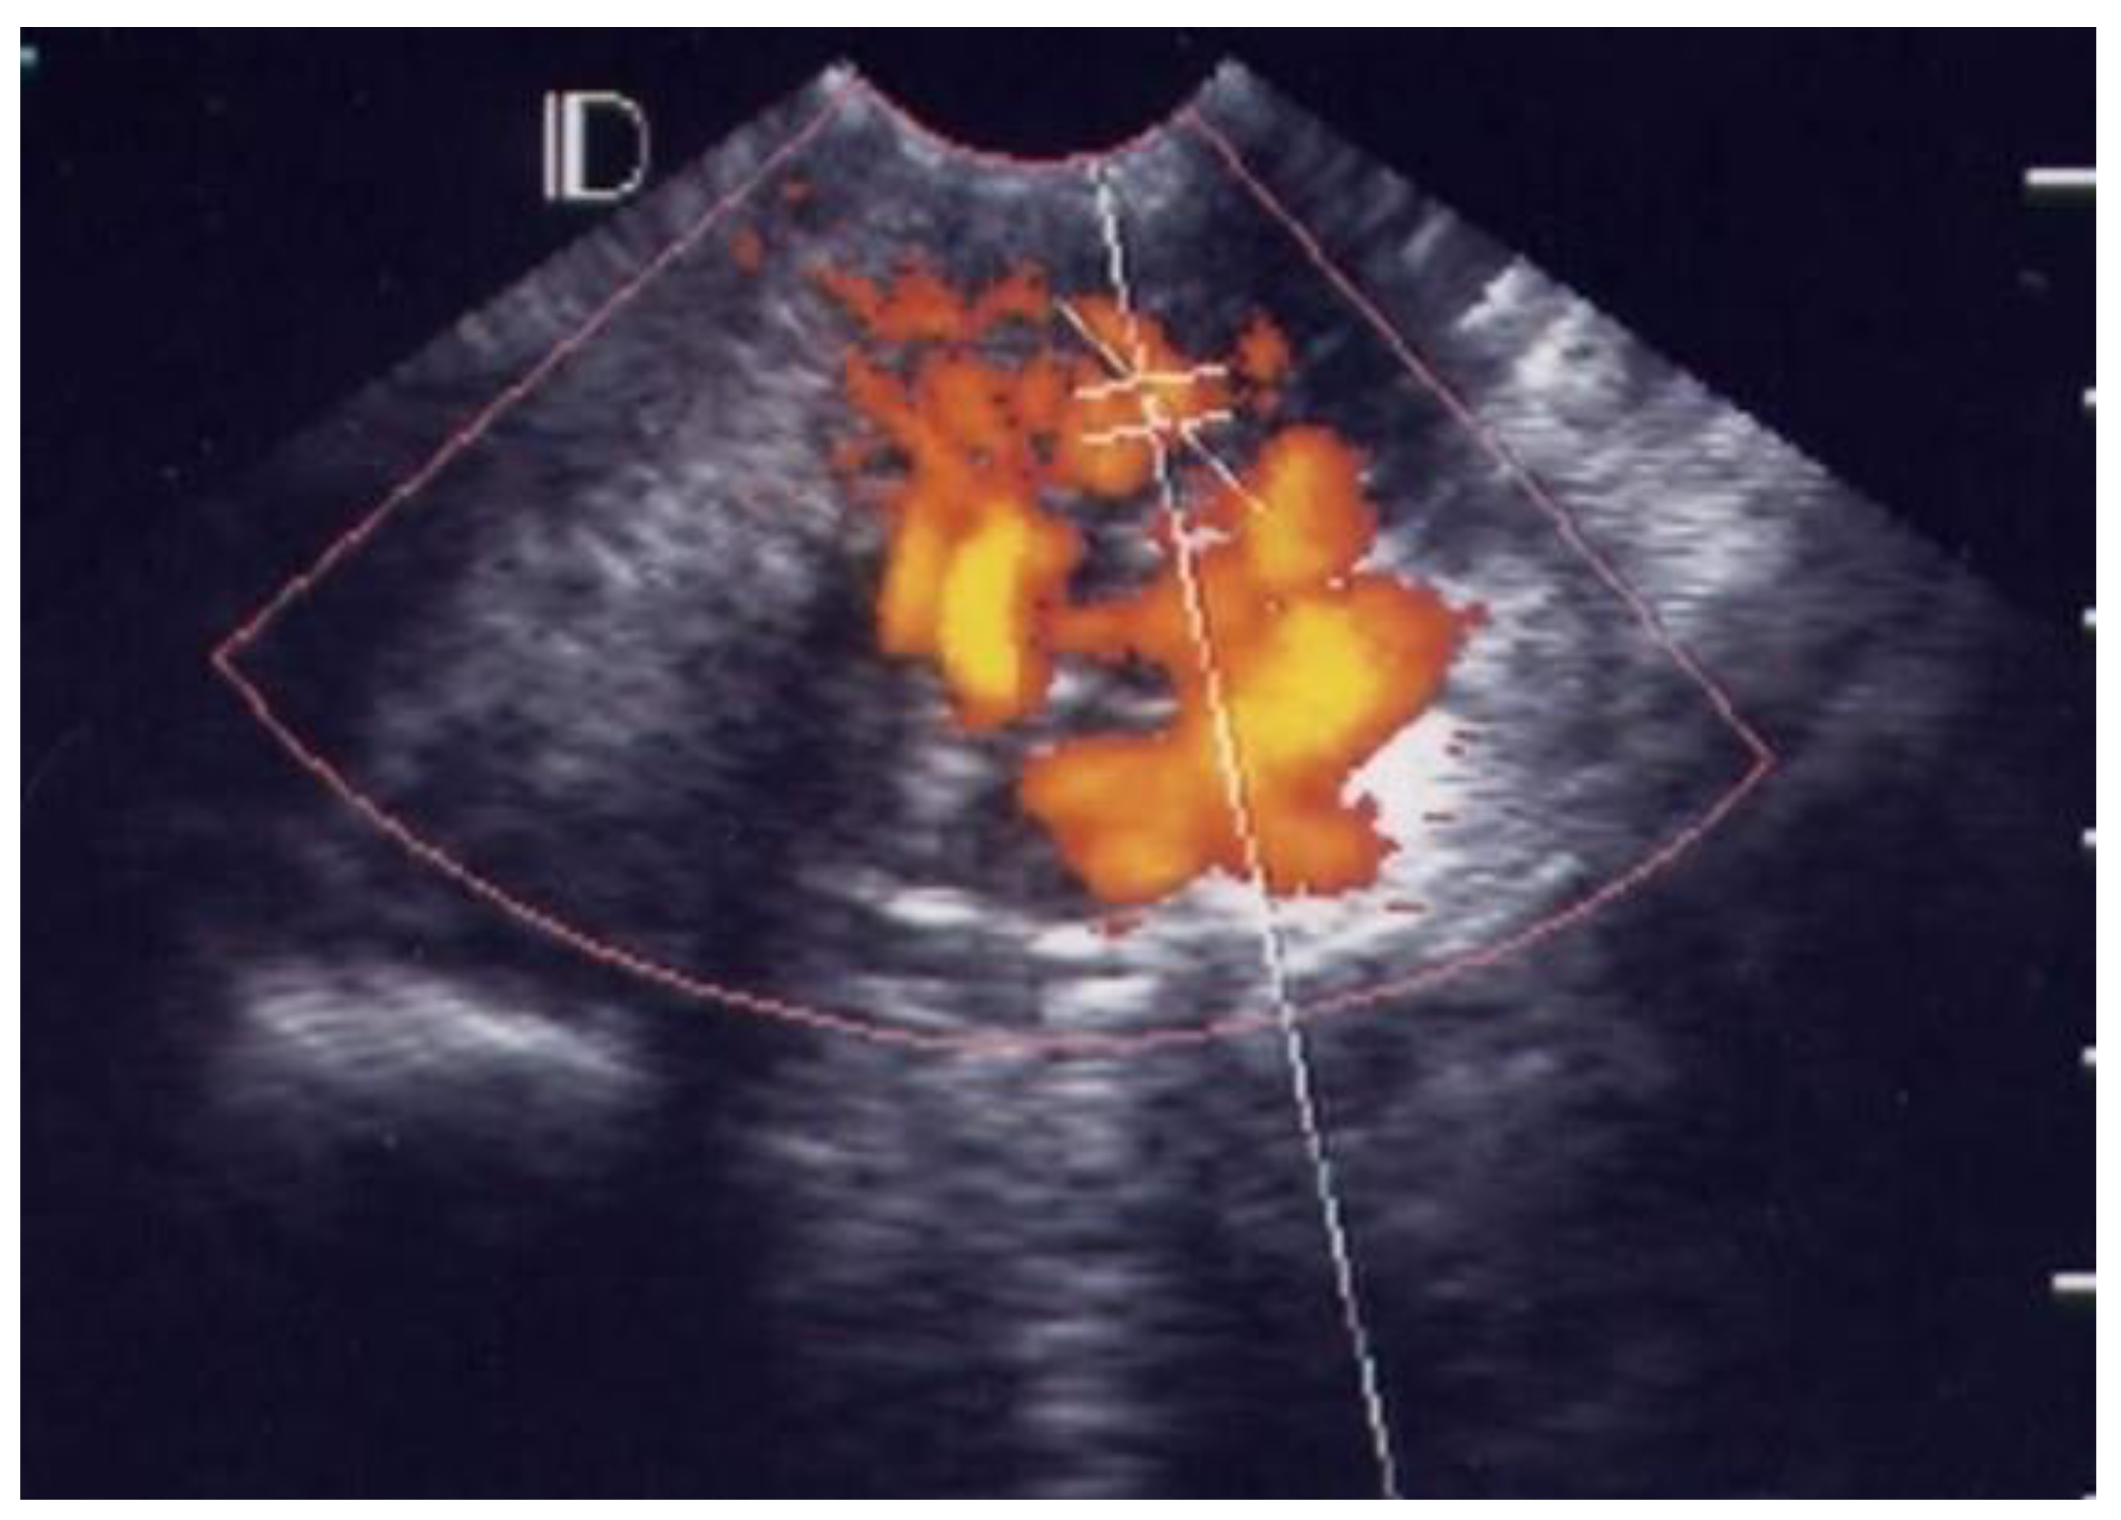

3.1. Visual Grading of Vascularity Findings on TV-PDU

| Grade 0 | Absence of vascular hot spot |

| Grade 1 | <5 vascular spots, not involve the endocervical canal |

| Grade 2 | >5 vascular spots, not involve the endocervical canal |

| Grade 3 | Involved the endocervical canal, without involved whole endocervix |

| Grade 4 | Involved the whole endocervix |